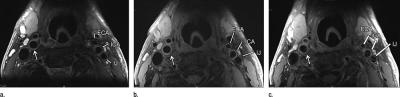

Researchers have long known that some arterial plaque is more dangerous because of its vulnerability to rupture. MRI can discern features of vulnerable plaque, such as a lipid core with a thin fibrous cap. This ability makes MRI a potentially valuable tool for identifying patients at risk for subsequent cardiovascular events.

To study the predictive value of MRI plaque imaging, researchers performed carotid artery ultrasound and MRI on 946 asymptomatic patients from the Multi-Ethnic Study of Atherosclerosis (MESA). The carotid arteries are the large vessels located on each side of the neck that carry oxygenated blood to the front part of the brain. They are highly accessible for imaging, and their condition tends to mirror that of the coronary arteries that supply the heart with oxygenated blood.

The researchers used ultrasound to assess carotid wall thickness and MRI to define carotid plaque composition and the remodeling index, a measure of changes in vessel size. Imaging results were compared with cardiovascular events, including heart attacks, stroke and death, for an average of 5.5 years after examination.

Cardiovascular events occurred in 59 of the patients. Abnormal thickening of the carotid artery wall and the presence of a lipid core and calcium in the internal carotid artery on MRI were significant predictors of subsequent events. A lipid core was present in almost half of the patients who had an event, compared with only 17.8 percent of those who did not have an event.